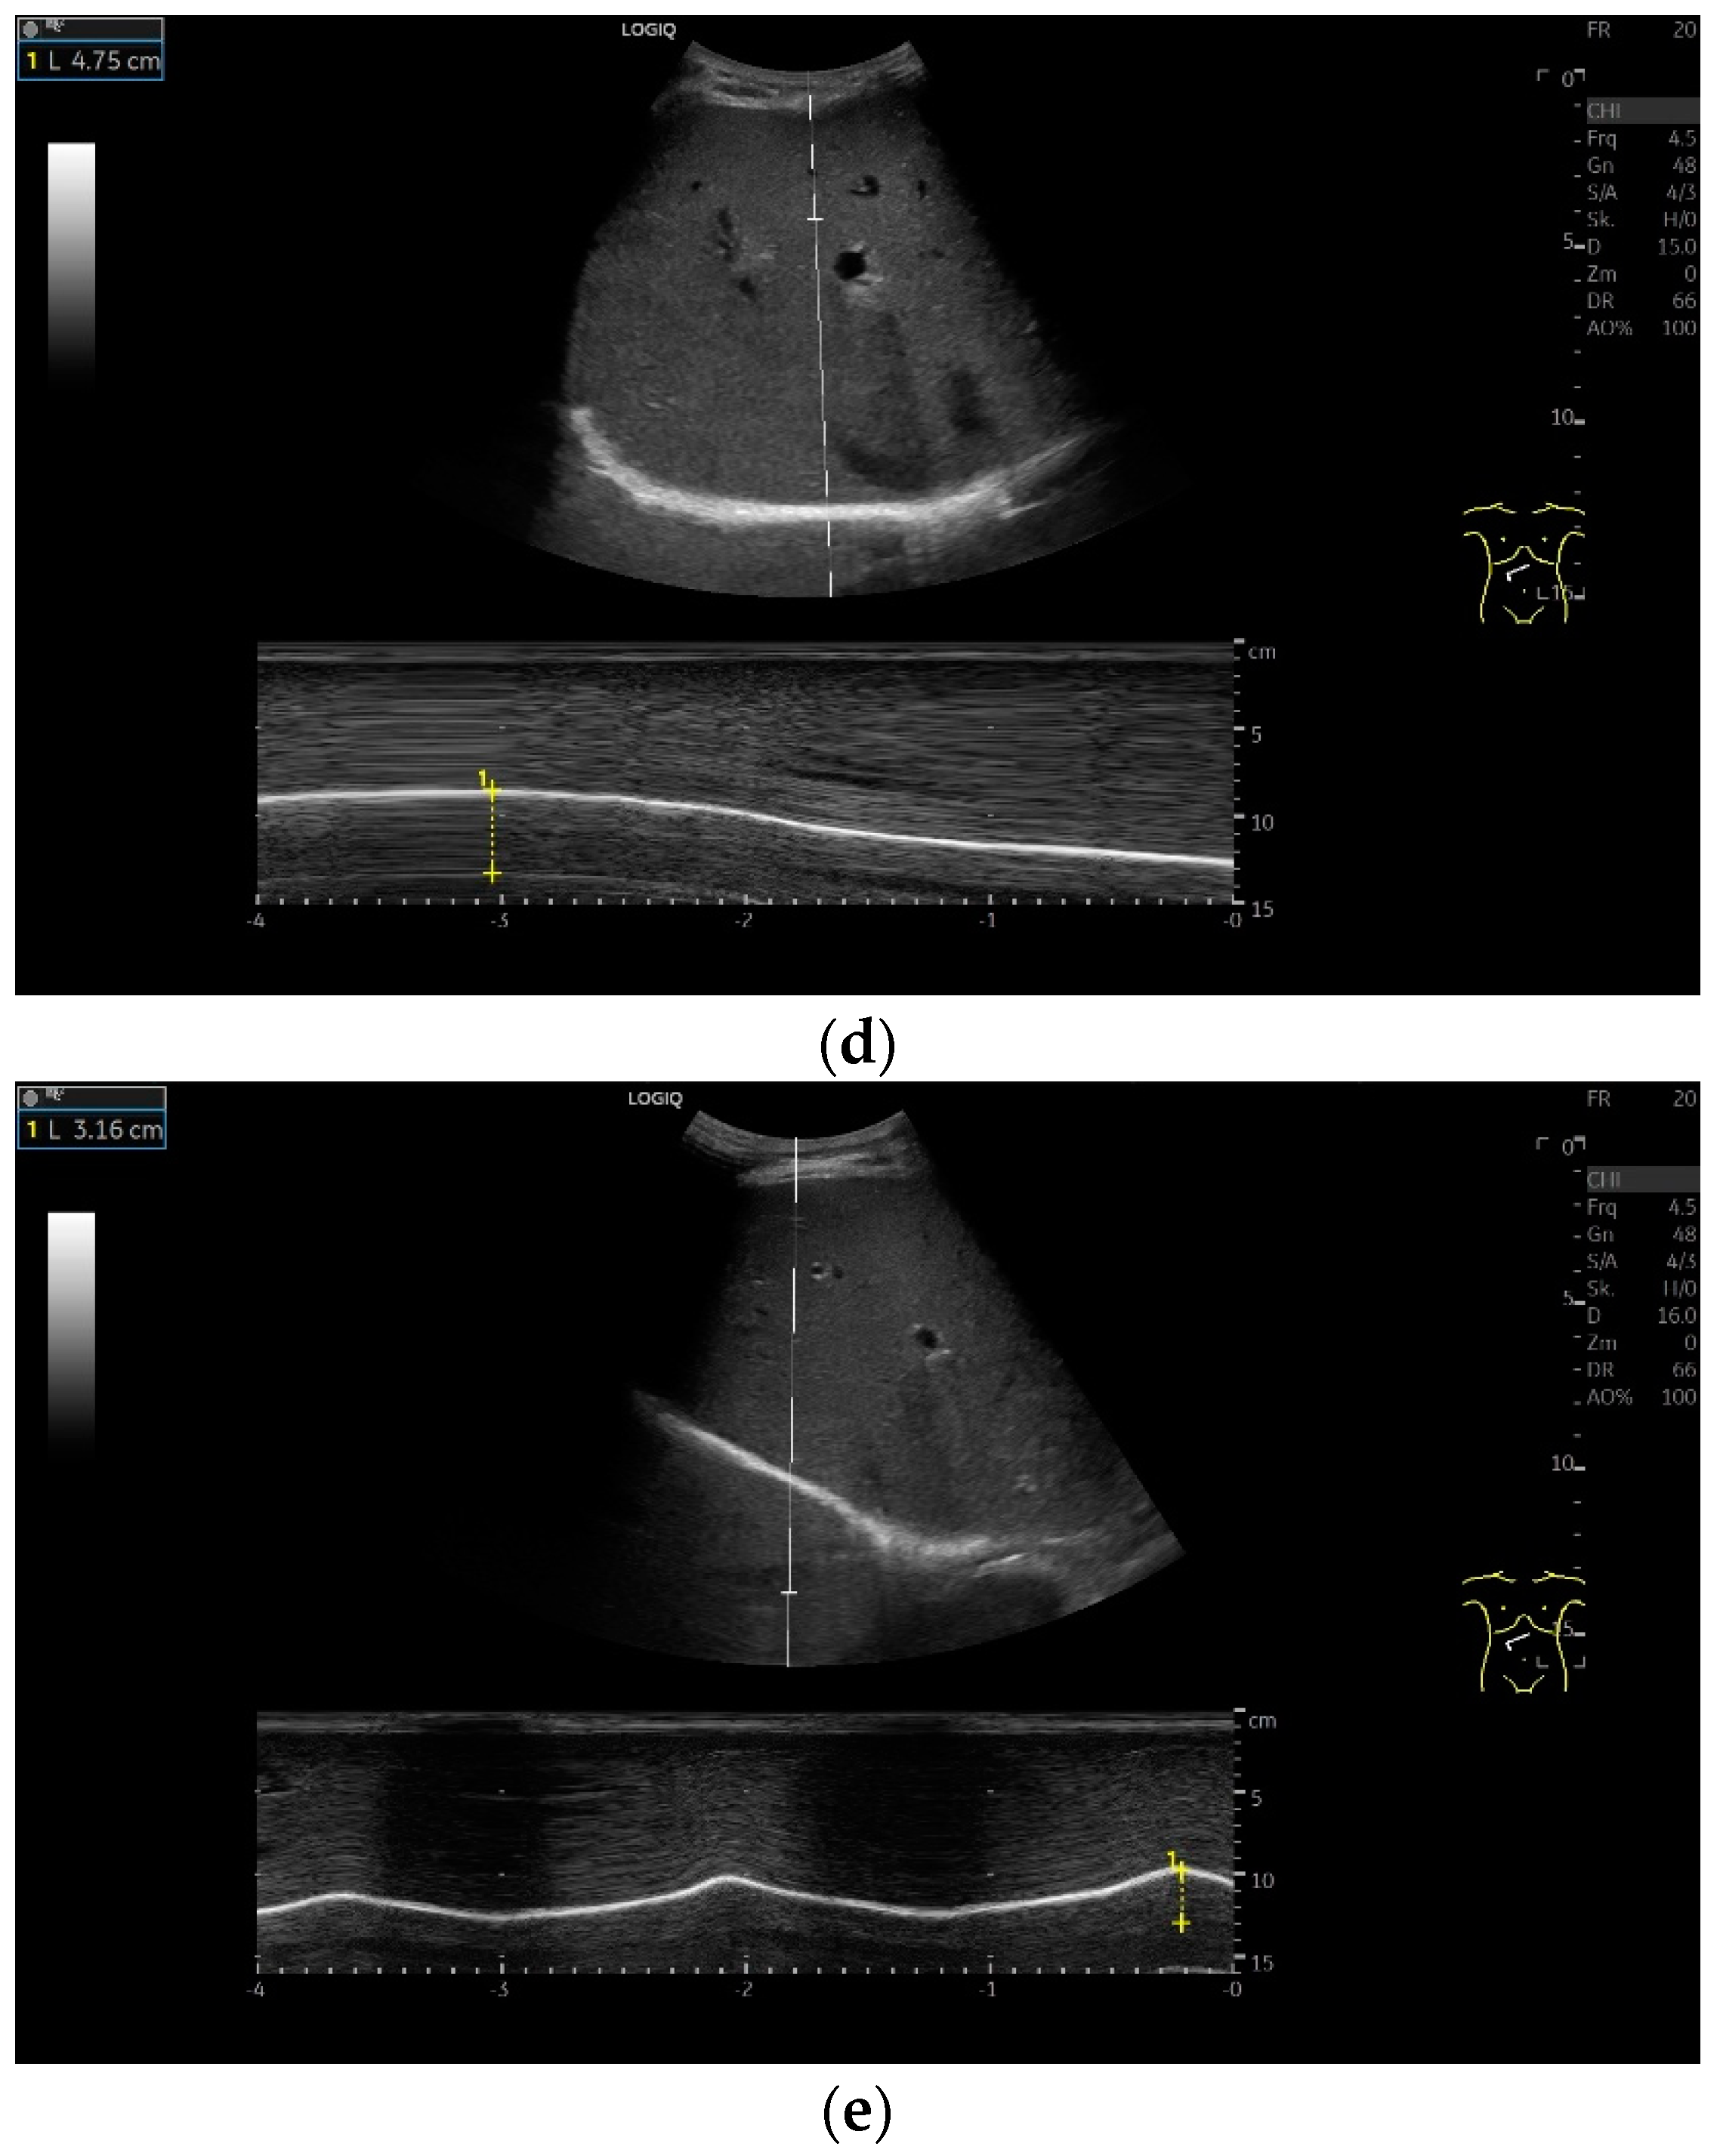

Subcostal transducer position: An abdominal sector or cardiac transducer (2–5 MHz) is used in the subcostal window. This position is used to assess diaphragmatic excursion. The transducer is placed between the linea medioclavicularis and linea axillaris anterior. The diaphragmatic excursion can then be visualized and measured in M-mode (Figure 5). The gallbladder and inferior vena cava are important landmarks. It is important to guide the ultrasound probe as perpendicularly as possible. The M-mode axis should meet the diaphragm at an angle of 90%. In this position, diaphragm thickness in inspiration and expiration can also be measured using M-mode, and diaphragm shortening can be calculated. However, in normal adults, the diaphragm can usually only be visualized in this position using abdominal sector transducers and is less accurately delineated than with a linear transducer from the lateral side in the anterior axillary line.